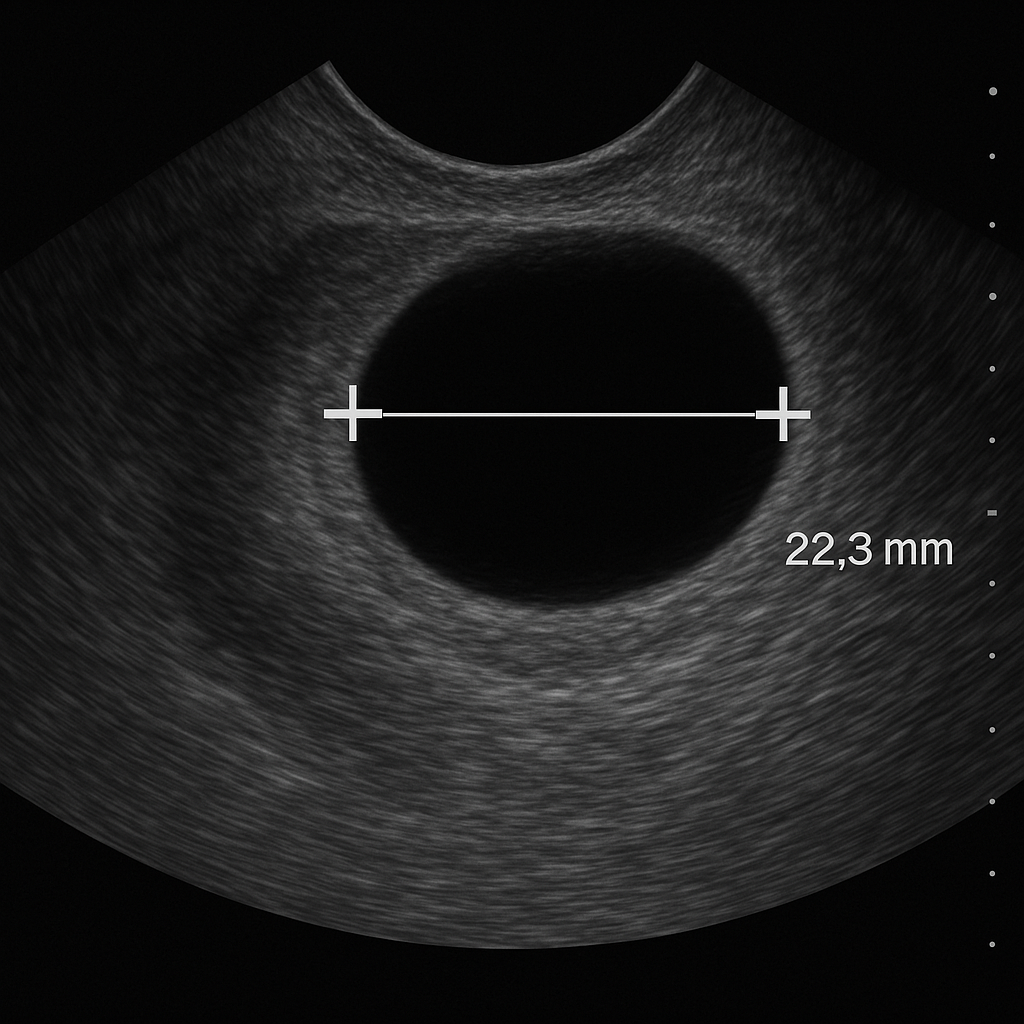

・エコー検査+尿ホルモン検査

エコーで卵胞の大きさを見て、市販と同様の尿検査で排卵日を予測します。1日前までにならないと排卵日はわかりません。そのため通院の回数が増えてしまいます。